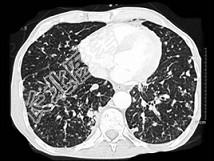

- 单项选择题女,56岁, 乳腺癌手术后,未行化疗, 结合CT图像,选择最可能的诊断是 ( )

A、肺转移癌

B、肺结核

C、间质性肺炎

D、肺结节病

E、肺曲菌病